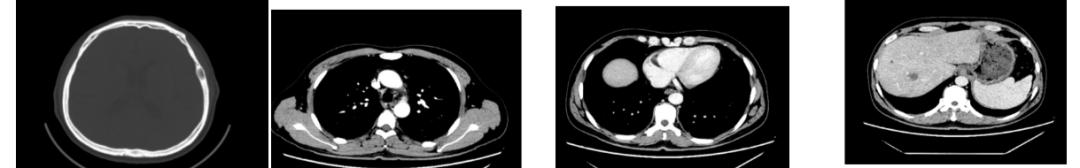

2020-06-18复查胃镜

胃镜:1、食管静脉曲张(中度)2、胃体肿物:Ca? 3、胃体息肉(已钳除)4、门脉高压性胃病;

病理内镜诊断:1、(胃体息肉)低级别腺瘤性息肉。HP(-)。2、(胃体肿物)高级别上皮内瘤变,因取材表浅,未见浸润,故未能诊断为癌;

胃癌并肝转移化疗后,肝内转移灶大致同期;

慢性肝病,脾大、门脉高压(食管下段-胃底静脉曲张);

双肾小囊肿;

右肺中叶外侧段、左肺上叶下舌段及右肺下叶后基底段慢性炎症;

右肺上叶前段实性微小结节,炎性结节?建议定期复查;

纵隔淋巴结转移瘤,复查大致同前。